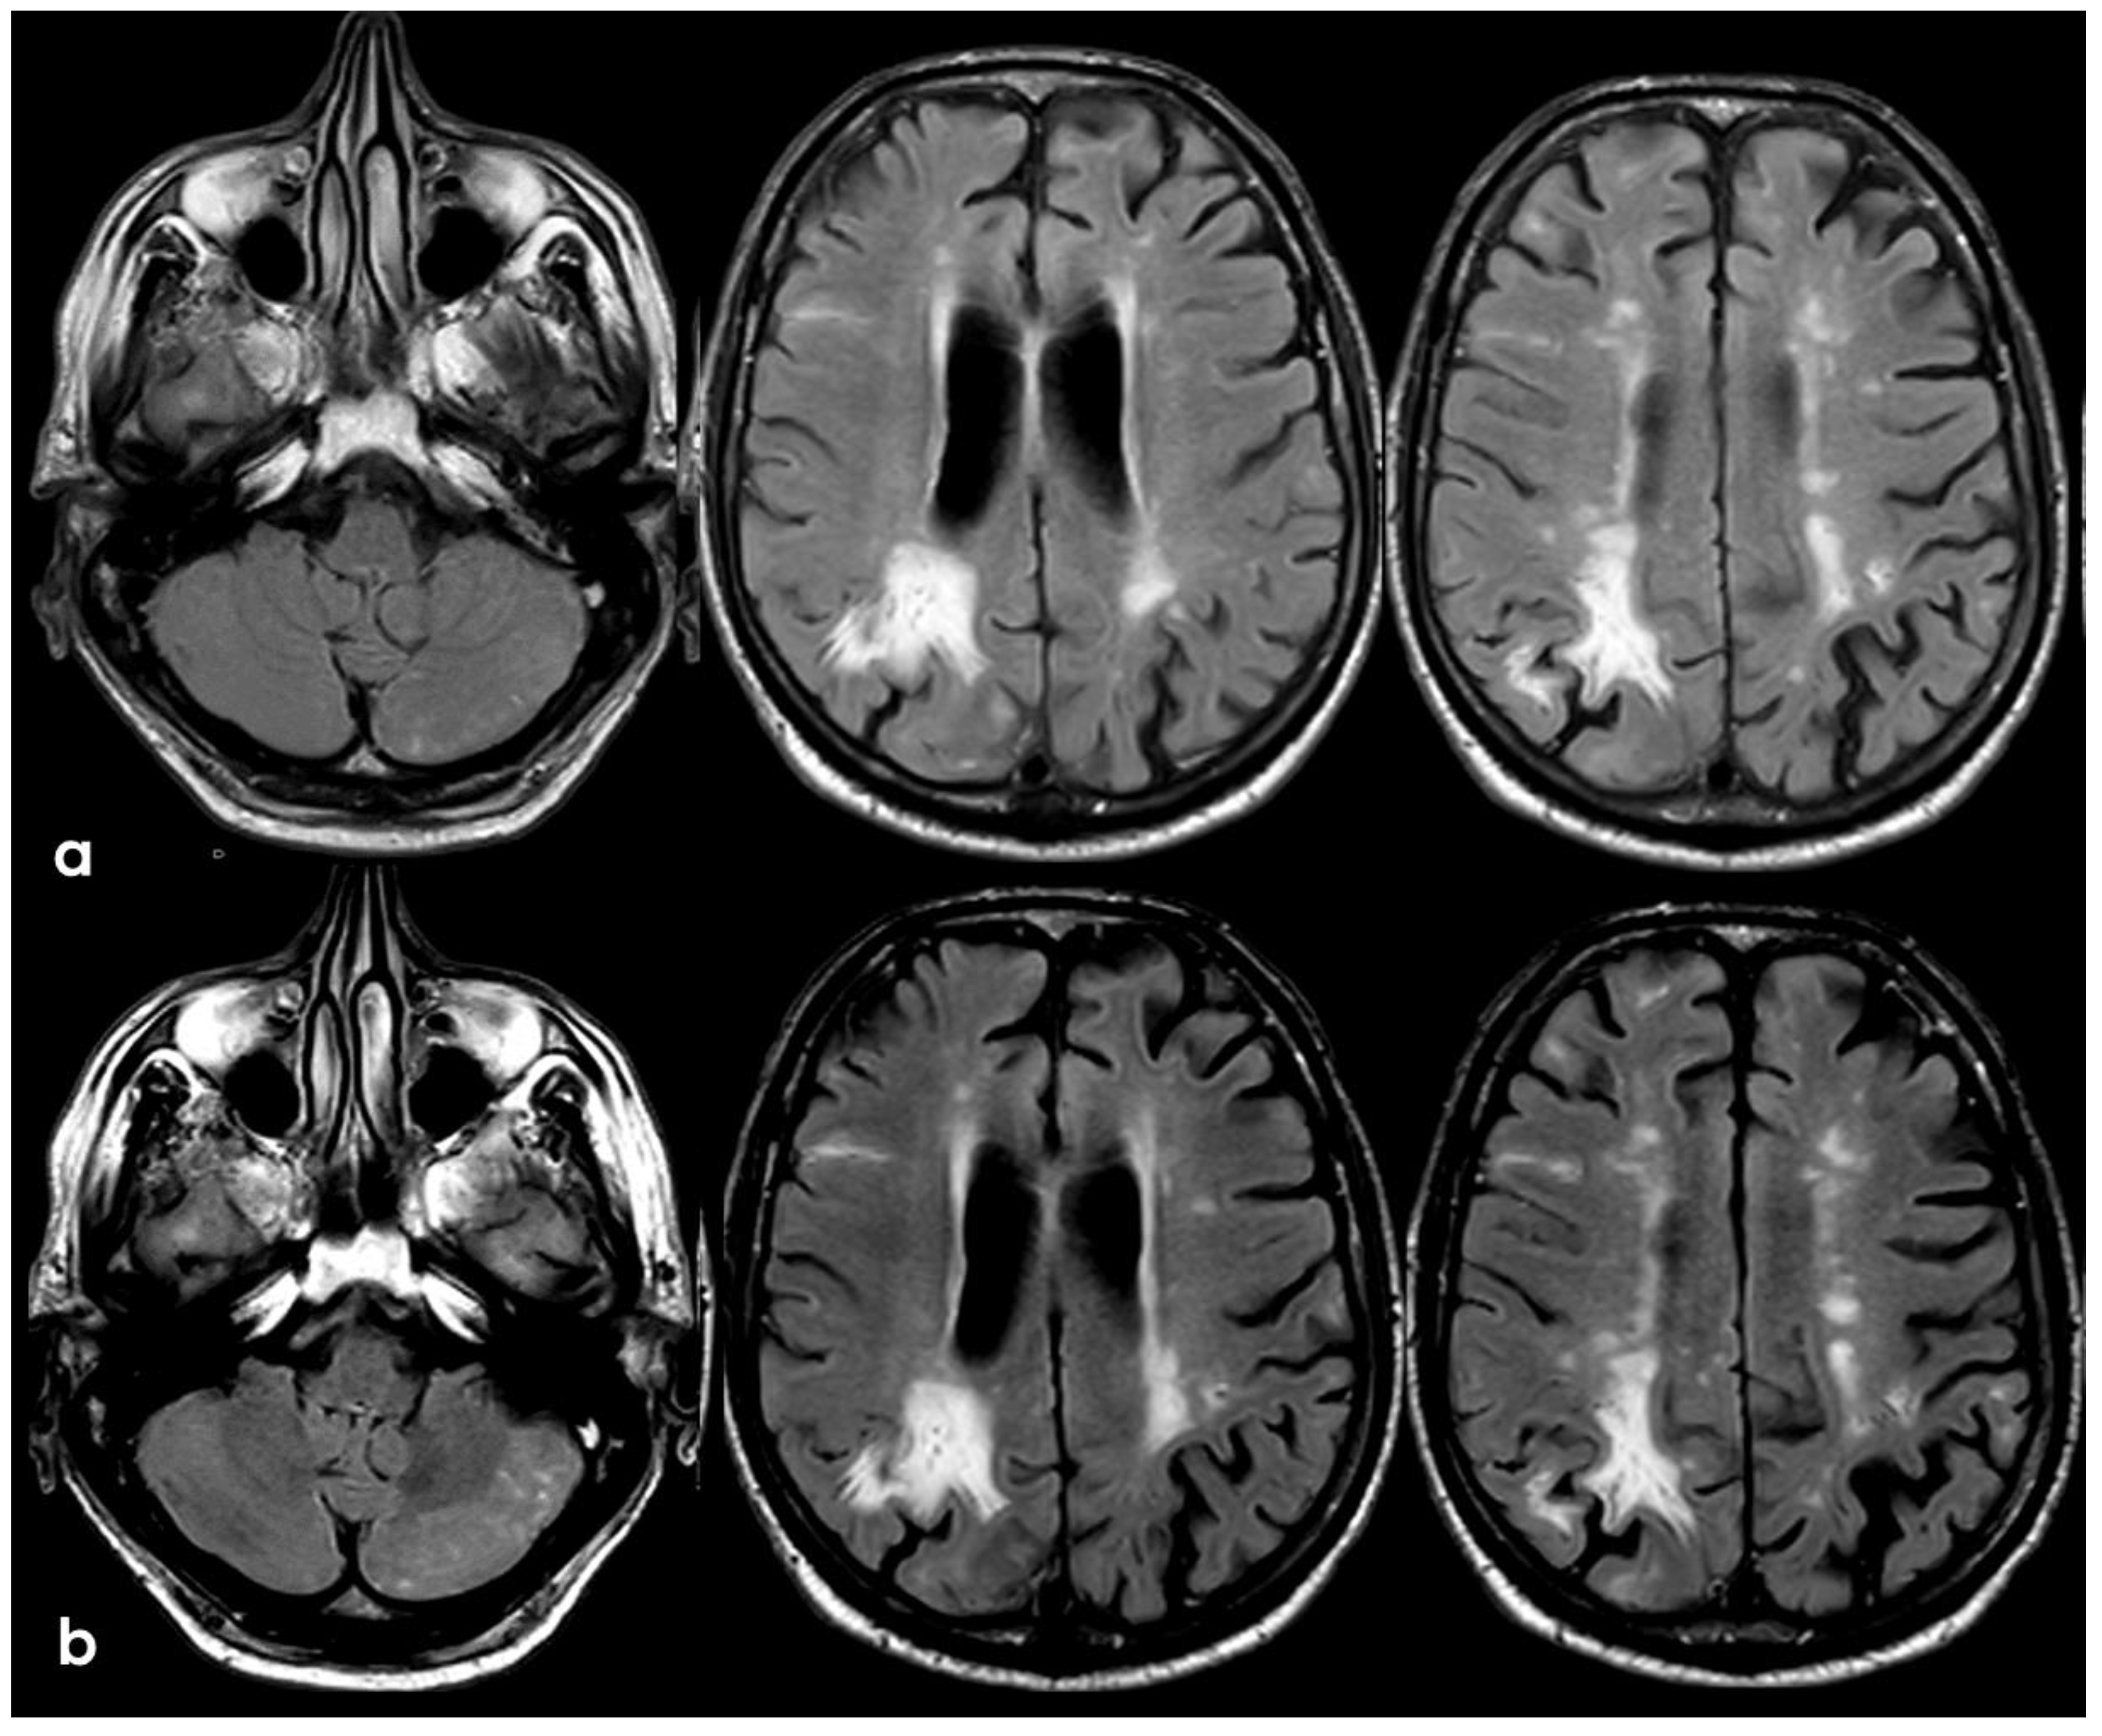

7. April 2018: Second Recurrent CAA-Related Inflammation

8. April 2018: Third Recurrent CAA-Related Inflammation